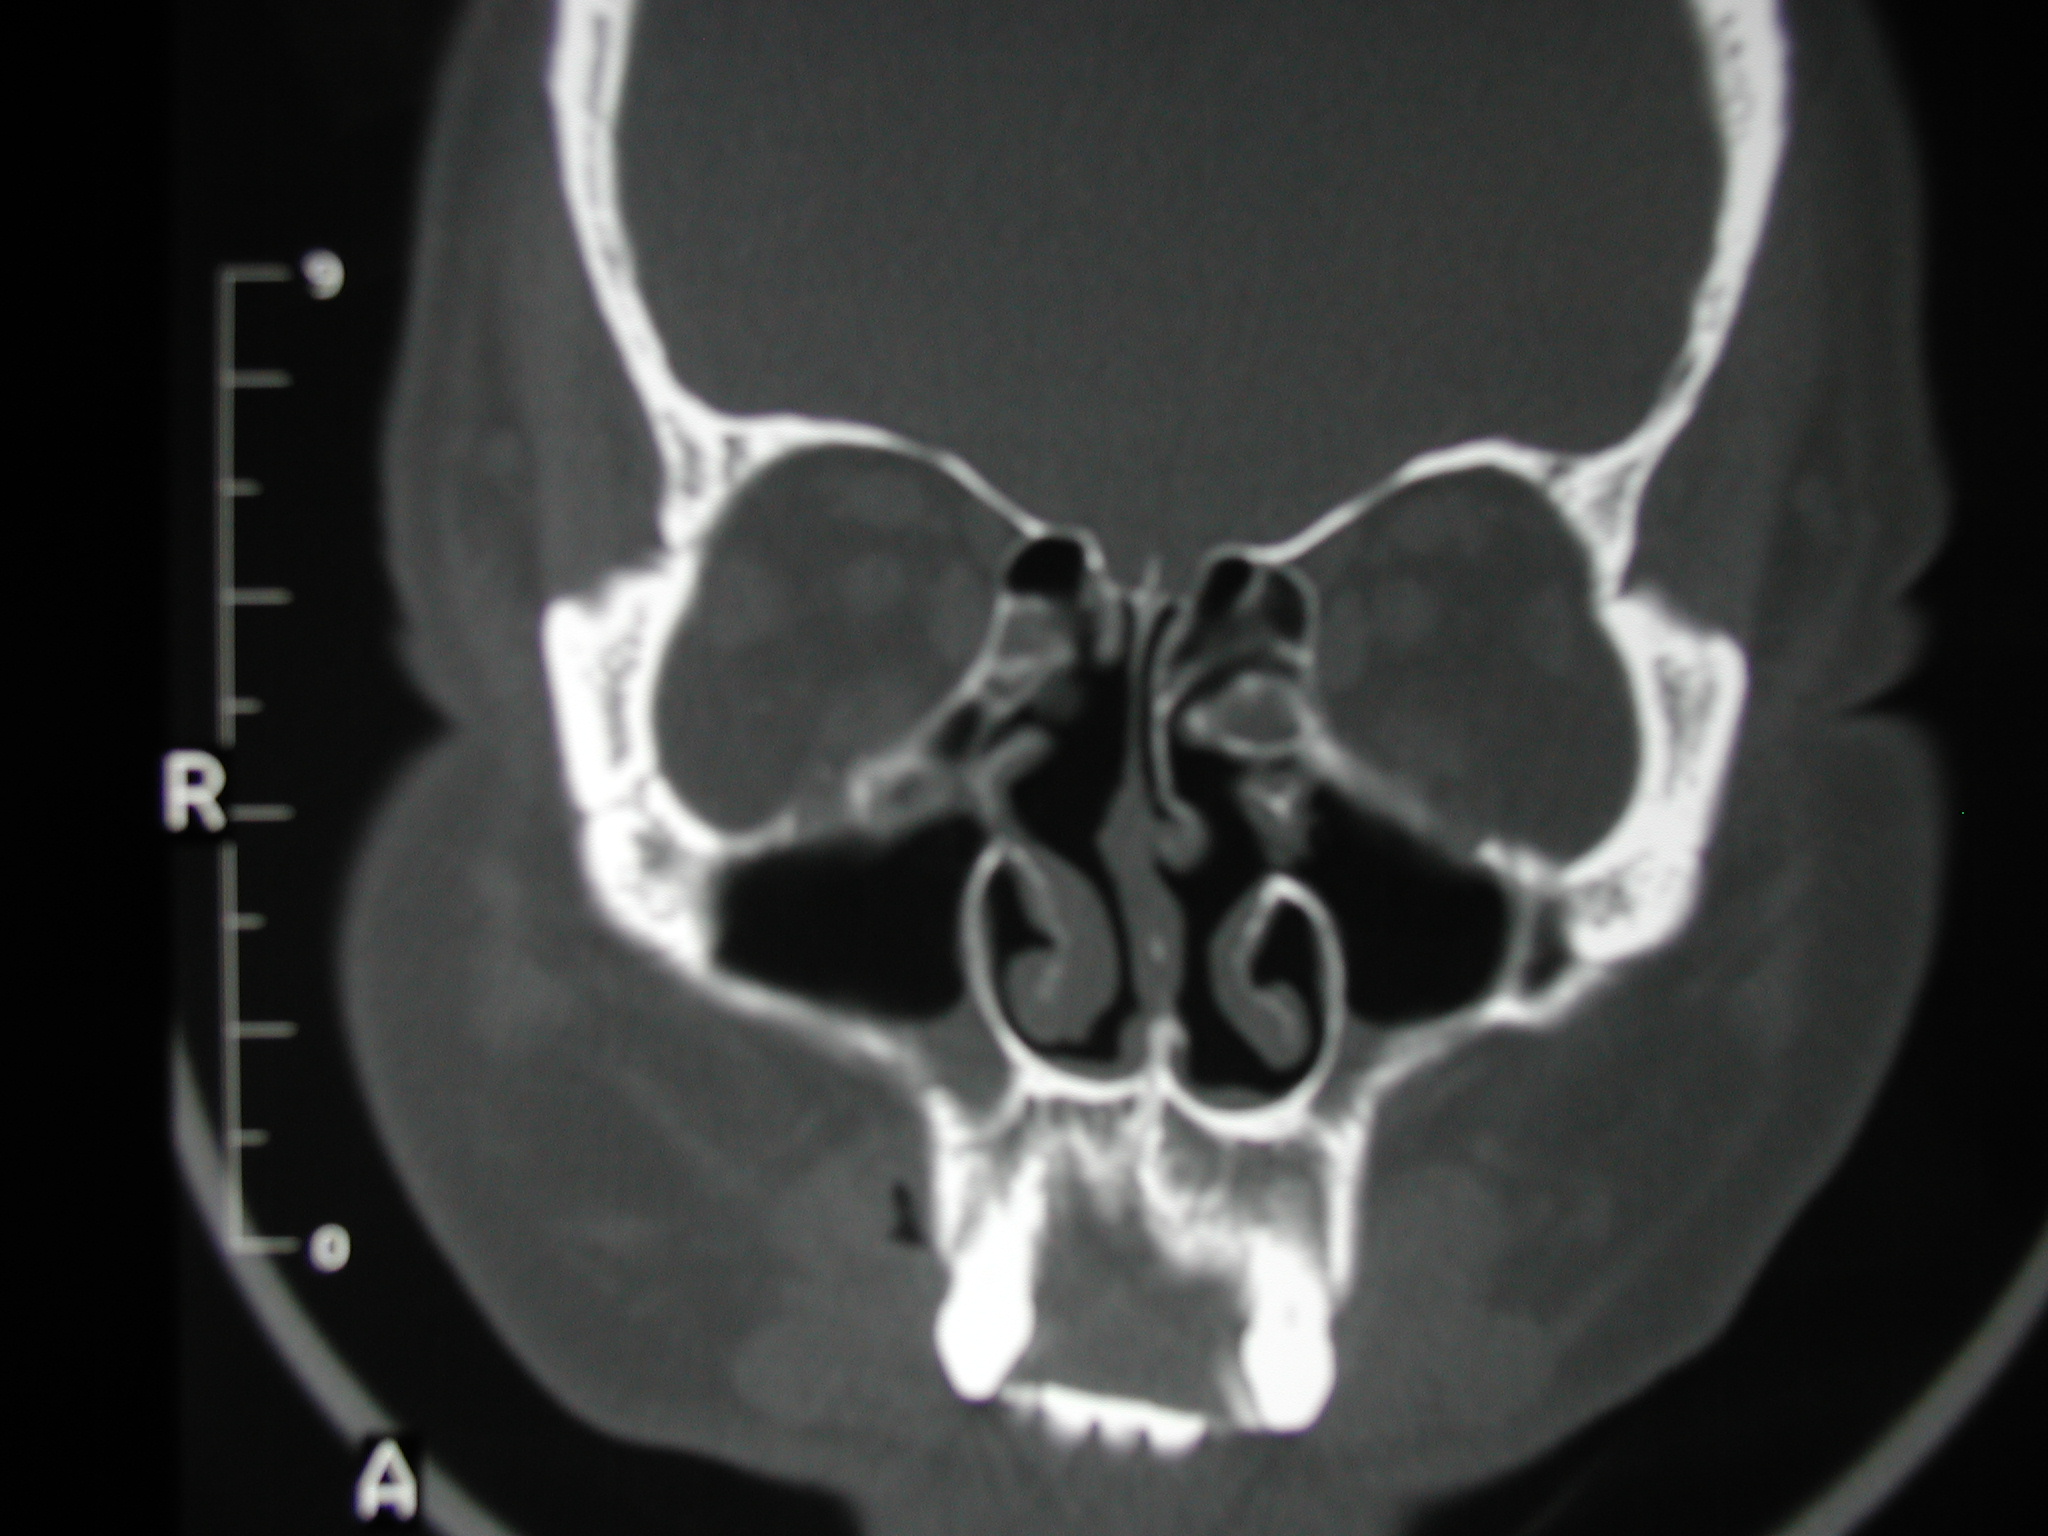

The patient above demonstrated clinical recirculation.  The intraoperative picture is located on another page.  The natural ostia are visualized in the first scan, and the large, though ineffective, iatrogenic ostia are seen in the second scan.